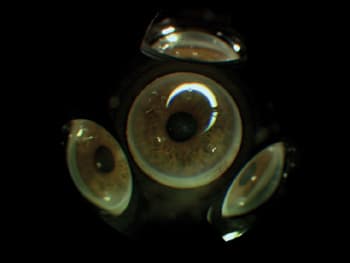

3.

The new 360° lens can be used for diagnosis and therapeutic applications. PHOTO CREDITS: MAT JOHNSON AND SYLVIA JONES. |

The new Volk 360 design provides clear angle details and 1.5 times magnification (see image 3, page 26). It affords a unique view of all angle structures simultaneously, which provides a panoramic view that far exceeds that achieved with standard three- or four-mirror lenses.

It requires no gonioscopic fluid (although I prefer to use one drop). It can be used with both standard slit-lamp illumination for diagnostic purposes and with laser light energy for therapeutic applications.

There are some drawbacks to the new lens. With certain slit lamps, the patient's face plane may be too close to the examiner to permit in-focus images; therefore an auxiliary forehead-rest cushion must be employed. (These are available from the manufacturer.) Another potential disadvantage is that the entire 360� view is lost when using higher magnifications.

However, overall I found the optics of this lens to be excellent and the "right-side-up" view with low magnification spectacular. It also makes the appreciation of the anterior chamber angle's beauty easy to demonstrate to my students.